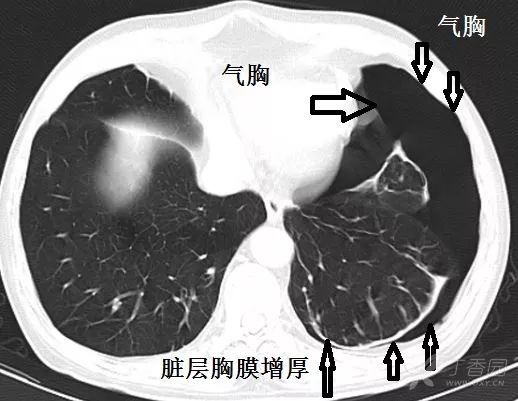

中叶支气管层面,气胸增多.